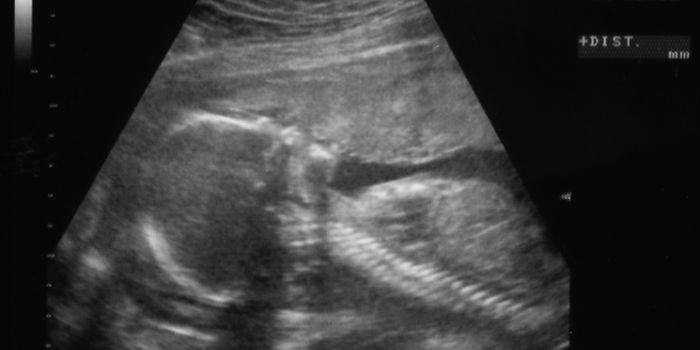

JUN 02, 2016Cell & Molecular BiologyMitochondrial replacement therapy was hailed as a promising new way to overcome diseases passed down in the DNA of mitoc ...

FEB 24, 2017Clinical & Molecular DXThe condition known as anencephaly – lacking a brain – affects about 3 pregnancies per every 10,000 in the U ...

OCT 16, 2017Clinical & Molecular DXThe precious fluid that protects a baby in the womb may also hold the potential to restore bone loss. Such discovery, re ...

JUN 11, 2016Clinical & Molecular DXThe controversial new procedure to create “three-parent babies” could be approved and available by as early ...

MAR 10, 2016Cell & Molecular BiologyScientists have found evidence that a lack of stem cells in the womb lining is causing thousands of women to suffer from ...

MAY 23, 2017Clinical & Molecular DXA 43-year-old mother in India became the first in her country to be a uterus organ donor. The recipient was her daughter ...

JUL 05, 2021Genetics & GenomicsFolate is necessary for a healthy pregnancy; low folate levels can lead to neural tube defects. A lack of folate, a nutr ...

NOV 18, 2016Clinical & Molecular DXFor women who have trouble conceiving naturally, assisted reproductive techniques like in vitro fertilization (IVF) can ...

JUL 15, 2016Clinical & Molecular DXAs soon as a woman becomes pregnant, her doctor will likely prescribe prenatal vitamins to help ensure the mom-to-be and ...

MAR 10, 2016Clinical & Molecular DXThe Cleveland Clinic reported that the first uterus transplant in the U.S. has sadly failed. The organ was removed on Tu ...

APR 11, 2016Clinical & Molecular DXA yeast infection was the root cause in the failure of the first uterus transplant in the US, doctors reported. The tran ...